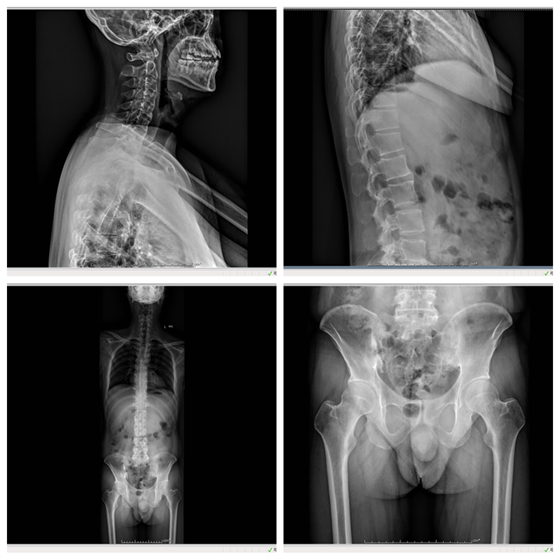

32岁的向先生,最近半年发现脖子不能左右转动,腰也不能弯,体重减轻了近10公斤。向先生说,自己30岁时就开始腰痛,一开始以为是“腰椎间盘突出”,自己吃药、贴膏药也时好时坏,后面经推荐吃了段时...